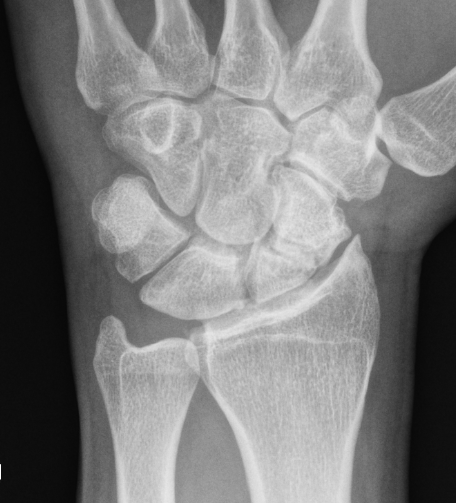

Rheumatoid wrist

SLAC wrist

SNAC wrist

Kienbock's disease